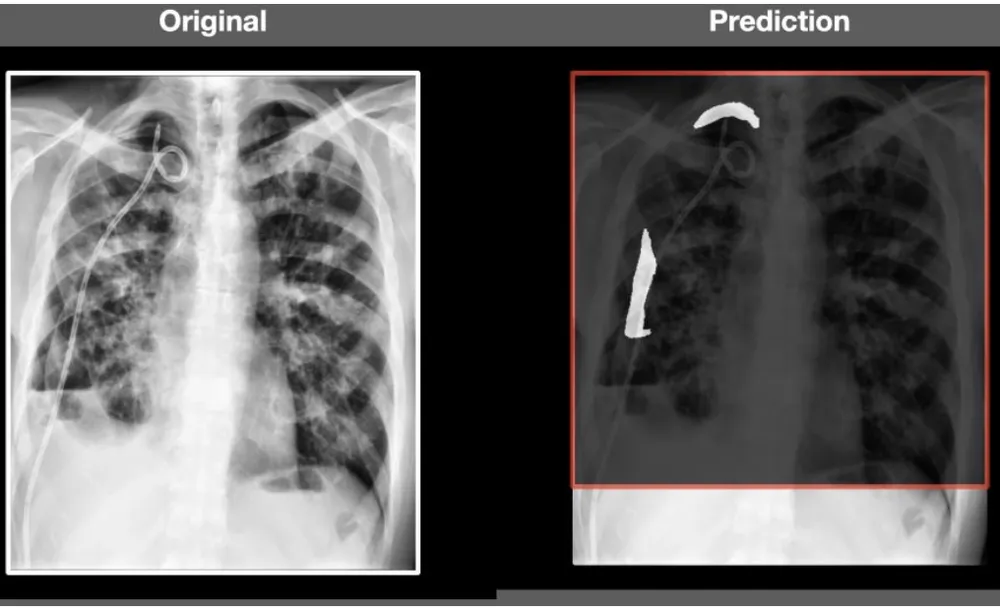

Cuộc thi thu hút 1.475 nhóm dự thi là các chuyên gia hàng đầu thế giới trong lĩnh vực nghiên cứu AI ứng dụng cho y tế. Tại cuộc thi này, dự án Ứng dụng trí tuệ nhân tạo phát hiện Tràn dịch khí màng phổi (Pneumothorax) của FPT Software đã giành huy chương Bạc.

| Để có được kết quả này, nhóm phát triển dự án đã thực hiện nhiều nghiên cứu sâu về các bài toán y tế; phối hợp với các bác sĩ, bệnh viện lớn trong cả nước, áp dụng các bài toán ứng dụng AI nhằm giúp cải thiện tình hình diễn biến phức tạp của bệnh tật trong hơn một năm. Đồng thời, nhóm cũng thực hiện áp dụng thuật toán trên tập dữ liệu lớn của Hiệp hội Ảnh Y tế Hoa Kỳ và Viện xương khớp Hoa Kỳ trong quá trình tham gia cuộc thi. |

| Tại cuộc thi này, thuật toán của FPT Software cho kết quả trung bình phát hiện bệnh ở thận và khối u lên tới 73% ( trong đó kết quả về phát hiện bệnh ở thận có độ chuẩn xác lên tới 93,9%, phát hiện ung thư là 56,6%). |